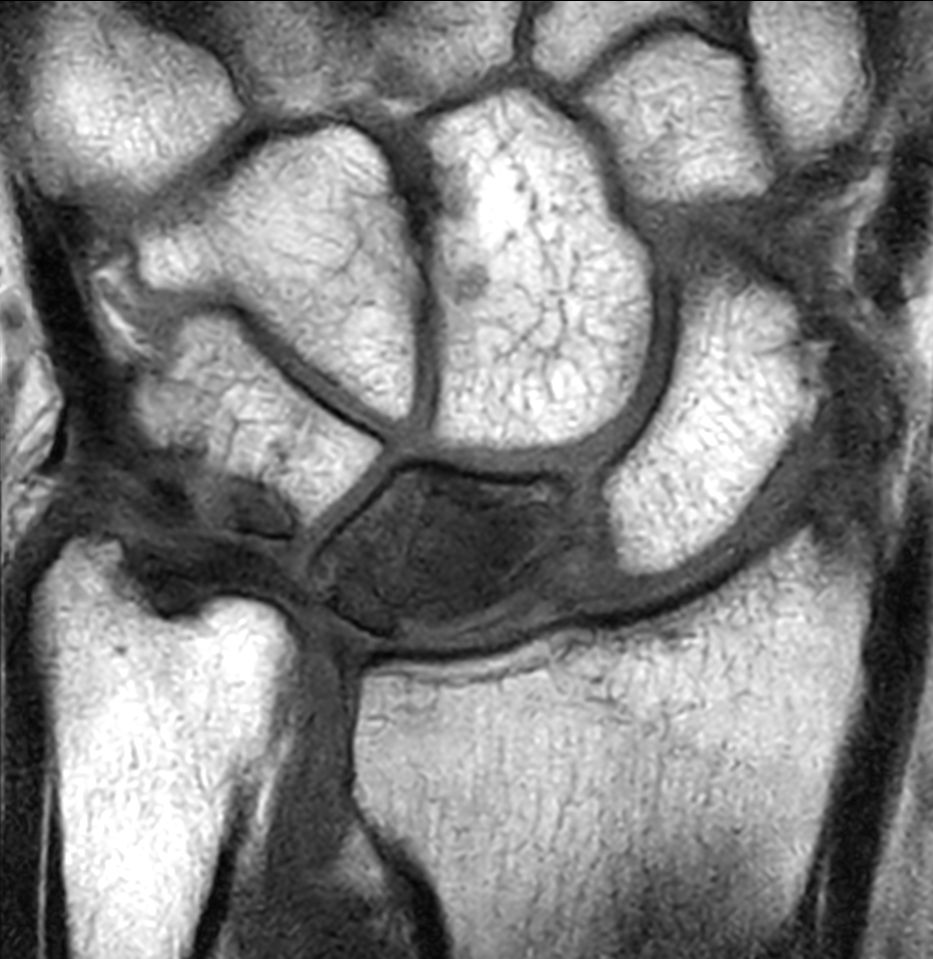

Patient with a lesion in his wrist. dS Microscopy coil set is used, consisting of two 47 mm coils, for small field-of-view imaging with high in-slice spatial resolution and a high signal-to-noise ratio. Compressed SENSE is used in all sequences to shorten the overall exam time for the patient.

Coronal T1w TSECompressed SENSE